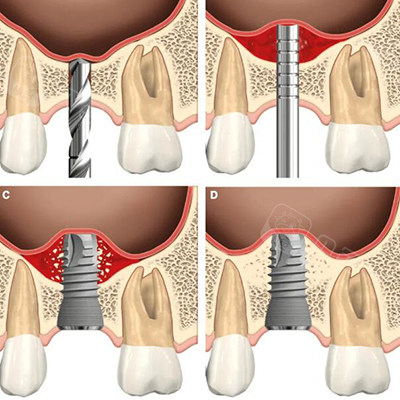

上颌窦 / gbr:sinus lift (crestal approach)

上颌窦提升是啥?看这个就知道了!